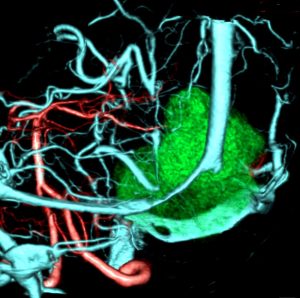

40代女性の後頭部傍矢状洞部の硬膜に発生したグレード3です。腫瘍周囲の強い浮腫のために,頭頂葉のゲルストマン症候で発症しました。術前診断は髄膜腫でしたが,腫瘍内部にのう胞(液体が溜まっている)があり,髄膜腫としては典型的な画像ではありません。右側の血管撮影にみられるように,上矢状洞が一部狭窄して腫瘍が浸潤している所見があり,腫瘍が濃染します。腫瘍の周囲の脳には出血がありました。大脳鎌と上矢状洞の壁を含めて全摘出しました。

この例でも,硬膜発生腫瘍ということは手術前の画像診断で解ってはいたのですが,髄膜腫と異なり不整な形をしてのう胞があり,一部は腫瘍壊死でした。

上の2例は,髄膜腫とは違うと一見してわかる,典型的なSFT/ヘマンジオペリサイトーマの例ですが,髄膜腫と鑑別できないようなものの方が多いです。